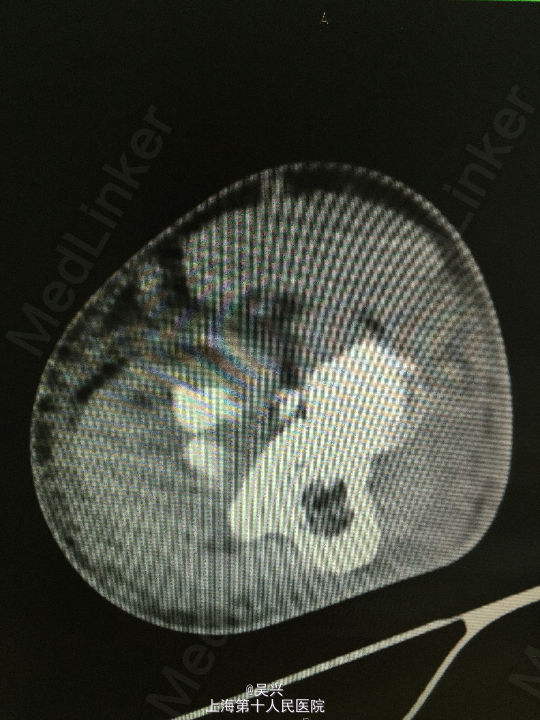

左肘外伤肿痛畸形3小时。左肘屈曲位着地受伤。

急症查体见肘关节肿胀、触痛,存在向后方半脱位及外侧松弛不稳定。

诊断:左肘恐怖三联症。 处理:术前准备,抗炎消肿治疗,术后三天行左肘正中切口显露尺骨冠状突,术中见尺骨冠状突粉碎性骨折,用两枚微型空心螺钉固定,发现屈肘位置仍有肘关节半脱位趋向。予伸肘位石膏固定,术后2周改屈肘45度位石膏固定,术后4周拆石膏,能逐渐屈肘至90度。

随访:术后1月患者肘关节稳定性良好,伸肘0度,屈肘90度,理疗辅助功能锻炼中。 讨论:肘关节脱位(半脱位)伴尺骨冠状突骨折、桡骨小头骨折称为肘关节恐怖三联症。该症存在极度肘关节不稳定,容易发生向后方、侧方脱位。一般单纯尺骨冠状突骨折极少,多伴有桡侧结构损伤和关节不稳定。肘关节恐怖三联症治疗原则一般是复位固定尺骨冠状突和桡骨小头,修复桡侧副韧带。我们术中发现固定尺骨冠状突后关节仍然不稳定,但桡骨小头因不全骨折需要石膏固定,因此不采取手术修复外侧副韧带,而是石膏固定,术后也取得较好的效果。